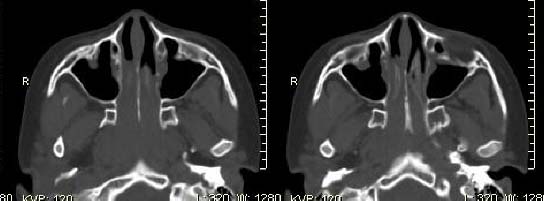

以下是引用随光逐影在2009-6-4 21:13:00的发言:[br]1)考虑鼻咽腺样体重度肥大。2)双侧鼻腔炎性改变。3)双侧上颌窦、双侧筛窦及左侧蝶窦炎症。

以下是引用zsl6918在2009-6-5 7:42:00的发言:[br]首先考虑鼻咽腺样体重度肥大,鉴别纤维血管瘤.强化有助明确.